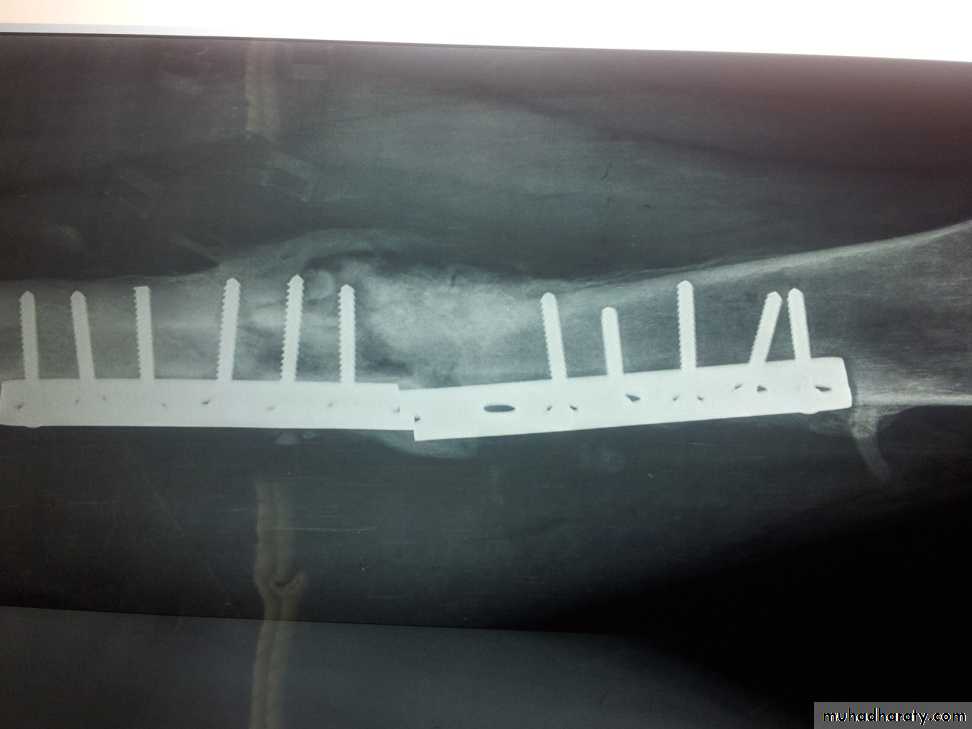

• Post traumatic and post operative osteomyelitis.

• 1)Post traumatic osteomyelitis.

• An open fracture may become infected

• It is the usual cause of acute osteomyelitis in adult.

• Bacteriology:

• The causative organism maybe multiple but staphylococcus aureus is the most common one.

• Clinical features: Fever, pain, swelling over the site of fracture.

• The wound is inflamed and there may be seropurulant discharge.

• Investigations: Elevated ESR and C-reactive protein (CRP) , Leucocytosis. ,,Wound swab sent for culture and sensitivity to identify the causative organism.

• Treatment: The wound should be left open for inspection and frequent dressing, and then delayed primary closure after few days. The fracture is fixed by external fixator.

• Appropriate antibiotic should be given from the beginning

• 2) Post operative osteomyelitis.;- It is not uncommon. ,,,,,The incidence in general hospital is 3-5%

• Predisposing factors.;- Debility.,,Previous infection,,Corticosteroid therapy. ,,,Haematoma formation.

• There is an increased risk with the use of foreign material (metal, plastics) for internal fixation or joint replacement.